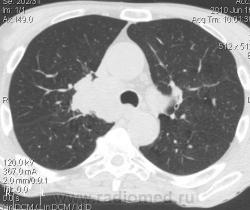

Мужчина 69 лет, с последствием ОНМК находился в доме-интернате для инвалидов. В анамнезе пневмония справа и исходом в пневмосклероз. ФЛГ не проходил 1.5 года. Анализы: СОЭ 20 мм/ч, остальное - без особенностей. Поступил в неврологическое отделение с диагнозом: повторное ОНМК. Невролог заподозрил метастазы головного мозга, направил на рентгенографию легких. После выявленых изменений в правом легком, пациент направлен на КТ головного мозга и грудной полости. От контрастирования и бронхоскопии категорически отказался.

По поводу подозрения на туберкулез пациента в прошлом нодократно проверяли, исключили. ФЛГ архива у меня нет. Все только со слов пациента. Кальцинаты в корне массивные. Трудно сказать, откуда опухоль (если это не конгломерат лимфоузлов!) плотностью 35 ед.Н - то ли из вехнедолевого бронха, который имеет культю 0.4 см и заканчивается выпуклым контуром, но при этом сохраняется воздушность почти всей доли; то ли периферический с центром в прикорневой зоне и вторичным прорастанием ВДБ. К сожалению забыла про снимок легких, на днях выставлю. Я первоначально считала периферический (верхушка, на фоне пневмосклероза) с мтс средостения. По плотности на верхушке узелок 5 ед.Н, только поэтому засомневалась, где же первичный. Лимфоузлы средостения множественные, до 2 см. Кроме того, на верхней стенке правого главного бронха есть мелкое образование такой же 35 е.Н плотности, то ли аденома, то ли прорастает... Без бронхоскопии - только гадать

это периферический рак S2 в/доли правого легкого с мтс во внутригрудные л/узлы.

А тут нечего гадать - данную демонстрацию можно поместить в учебник: узловое образование, с бугристыми, лучистыми контурами, связаное с плеврой, "дорожкой" к корню, перифокальной инфильтрацией. Корень расширен полицикличен за счет конгломерата увеличеных бронхопульмональных, трахеобронхиальных и бифуркационных л/узлов, значительно сдавливающих в/долевой бронх, с нарушением вентиляции в/доли.

Центральный рак ВДБ справа с мтс в л/узлы паратрахеальные нижние, верхние справа, БФ. МТС в головной мозг. А про печень мало сканов

Мне кажется в 6 сегменте печени мтс + еще мтс поражение левого надпочечника вероятнее всего. Мтс в нижние паратрахеальные (с обеих сторон)+бифуркационные л/у. Поражения верхних паратрахеальных не вижу (на коронарах), аксиалы - не показыны сканы выше верхнего края дуги аорты, так что я бы не говорил про поражение верхних медиастинальных лимфоузлов (хотя тут это уже не принципиально) + мтс в головной мозг. А так - центральный рак правого легкого.